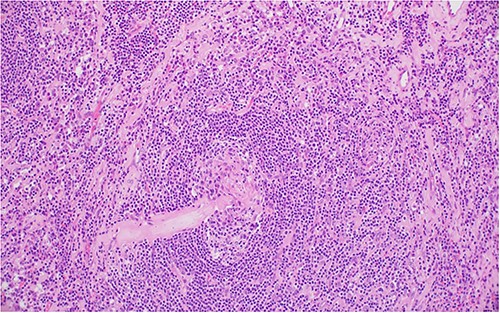

The patient underwent right laparoscopic adrenalectomy with a transperitoneal approach. A dark yellow tumor measuring 11 × 7 × 3.5 cm was removed en bloc (Fig. 2). Postoperative convalescence was uneventful and the patient was discharged home after 2 days, with discontinuation of antihypertensive medications. Microscopic examination revealed a mixed hyaline vascular and plasma cell variant type of Castleman lymphadenopathy (Figs 3 and 4). Immunohistochemistry showed a mixed pattern of CD20 and CD3, IgD that highlighted the expanded mantle zones and CD138-positive plasma cells that showed polytypic expression of Kappa and lambda immunoglobulin light chains. Immunostaining for Human herpesvirus 8 (HHV-8) was positive. A diagnosis of a unicentric mixed variant of Castleman lymphadenopathy was made.

Two germinal centers fused and surrounded by one mantle zone—‘twinning’.